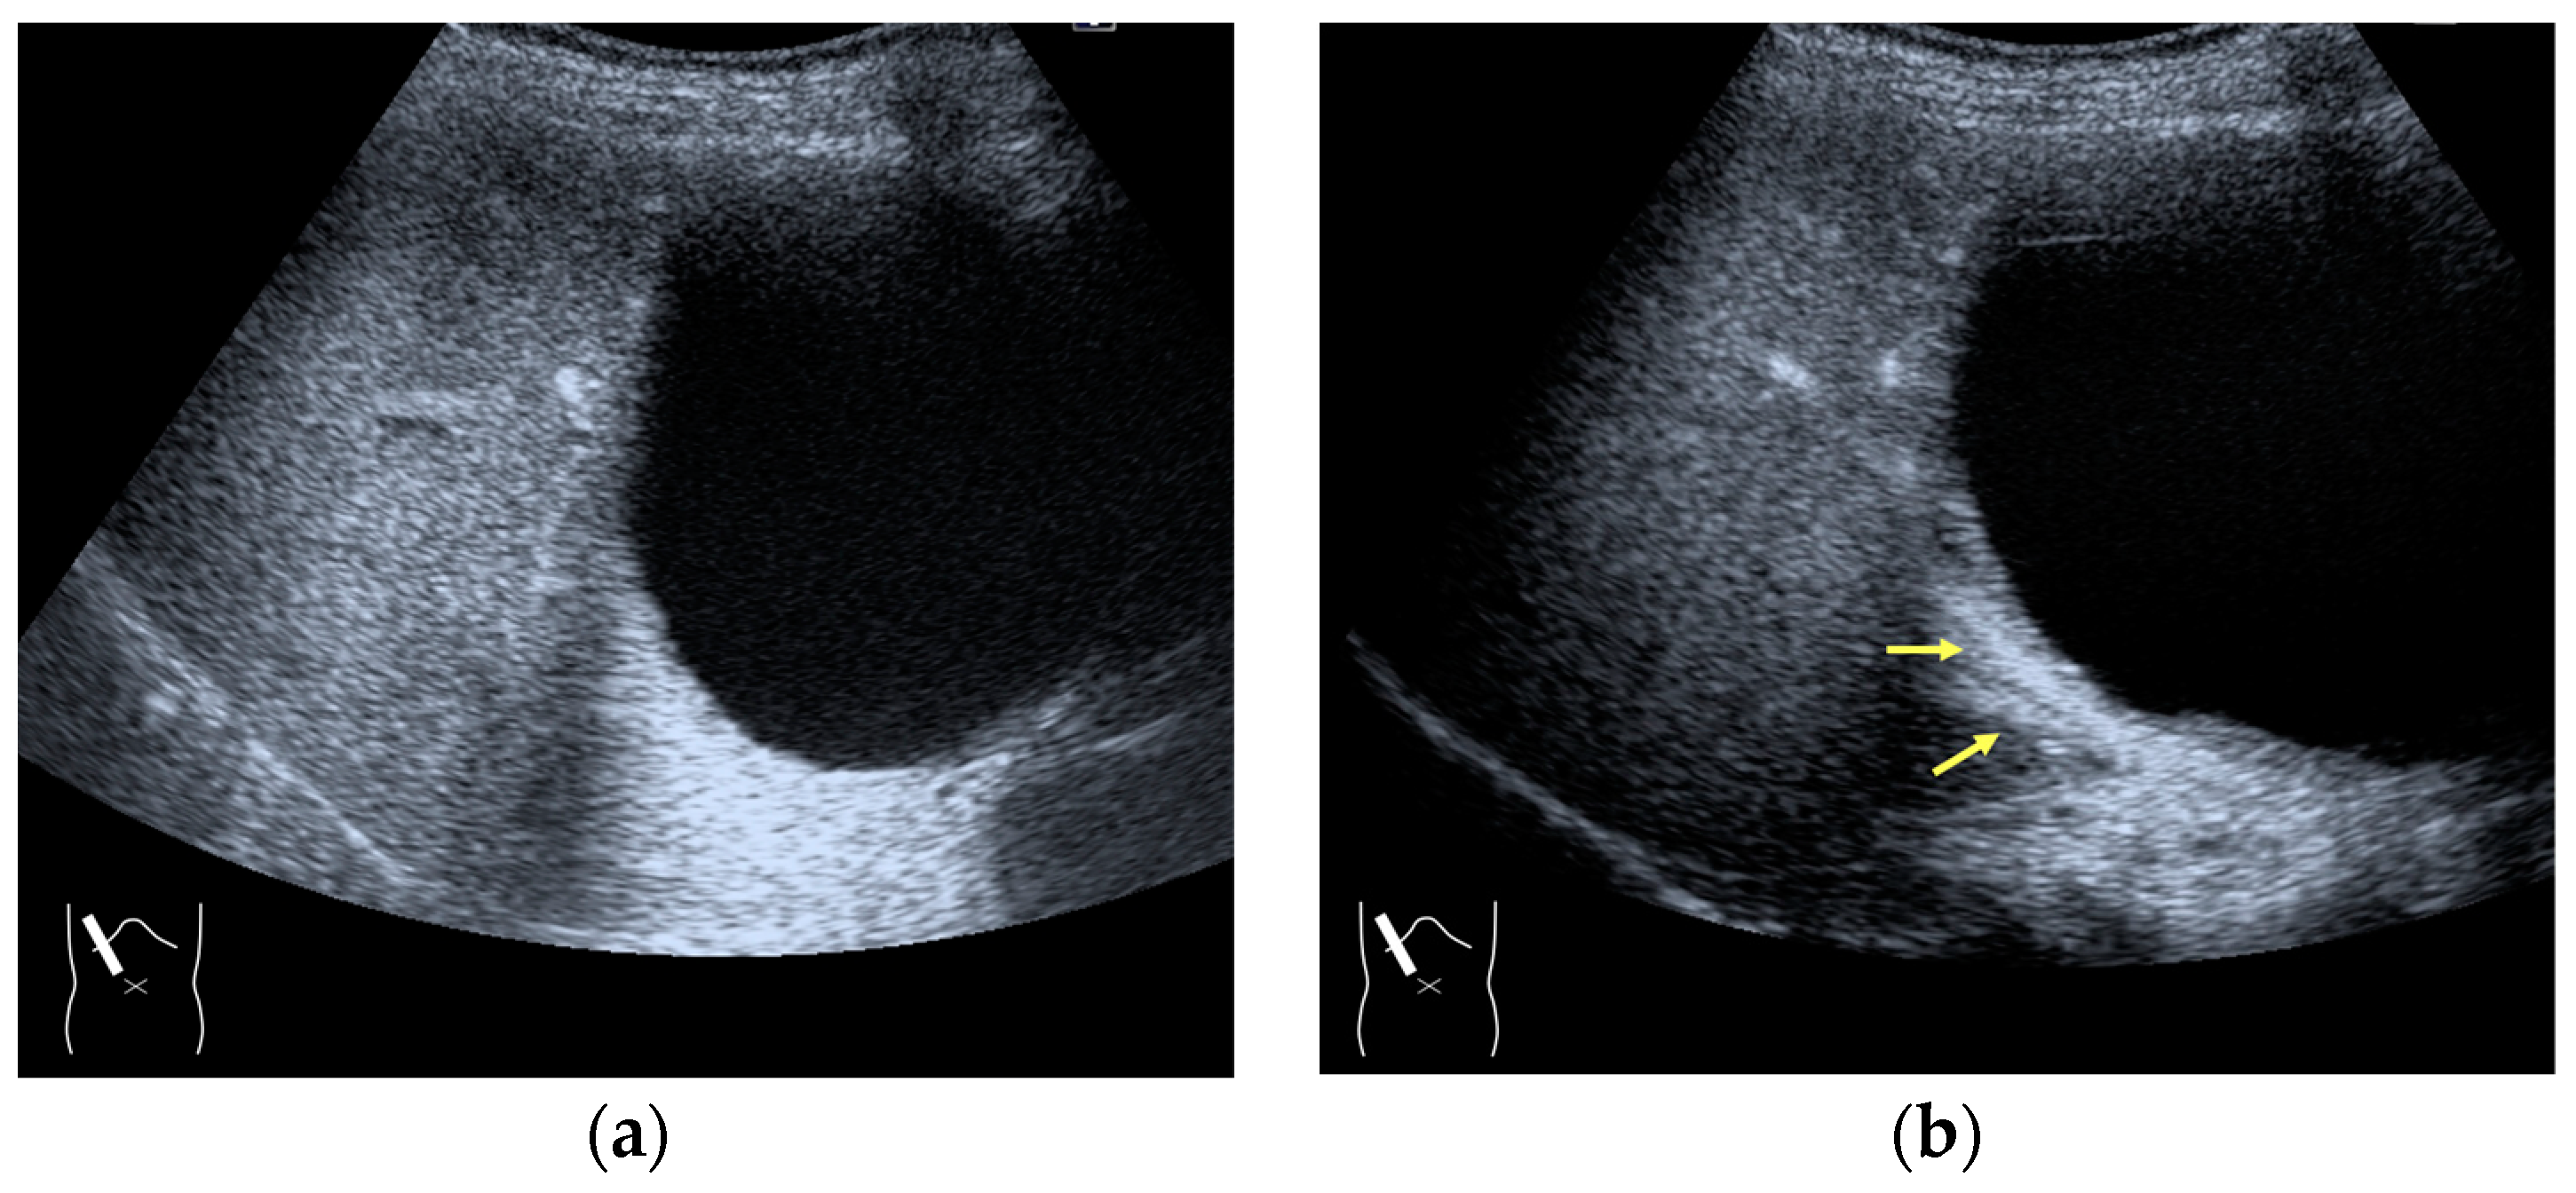

Figure 9.

Representative case of a sound attenuation artifact. The presence of massive ascites leads to US beams passing through less attenuated ascites, mimicking an echogenic liver tumor (arrows). (a) B-mode US and (b) CEUS.